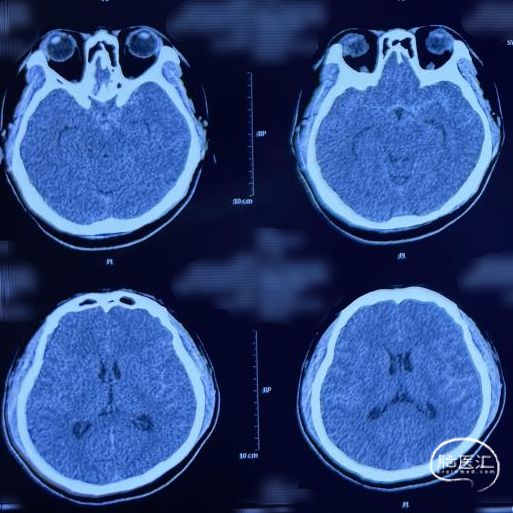

患者男性,40岁。

主诉:突发头痛约4小时。

查体:神清语利,颈项强直,四肢活动正常。Hunt-Hess 1级。

急诊头颅CTA:左侧大脑中动脉M1远端分叉处动脉瘤,左侧大脑中动脉M1段颞干分叉处动脉瘤。